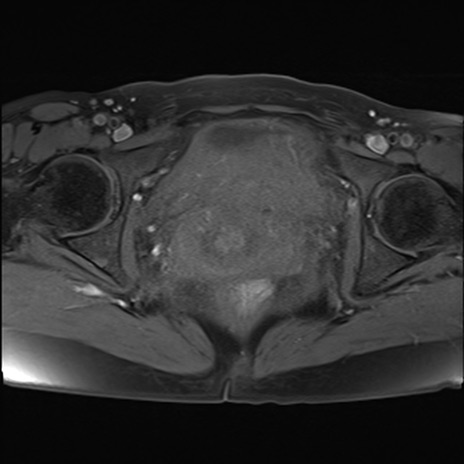

MRI(4日後)

T2WI(横断像)